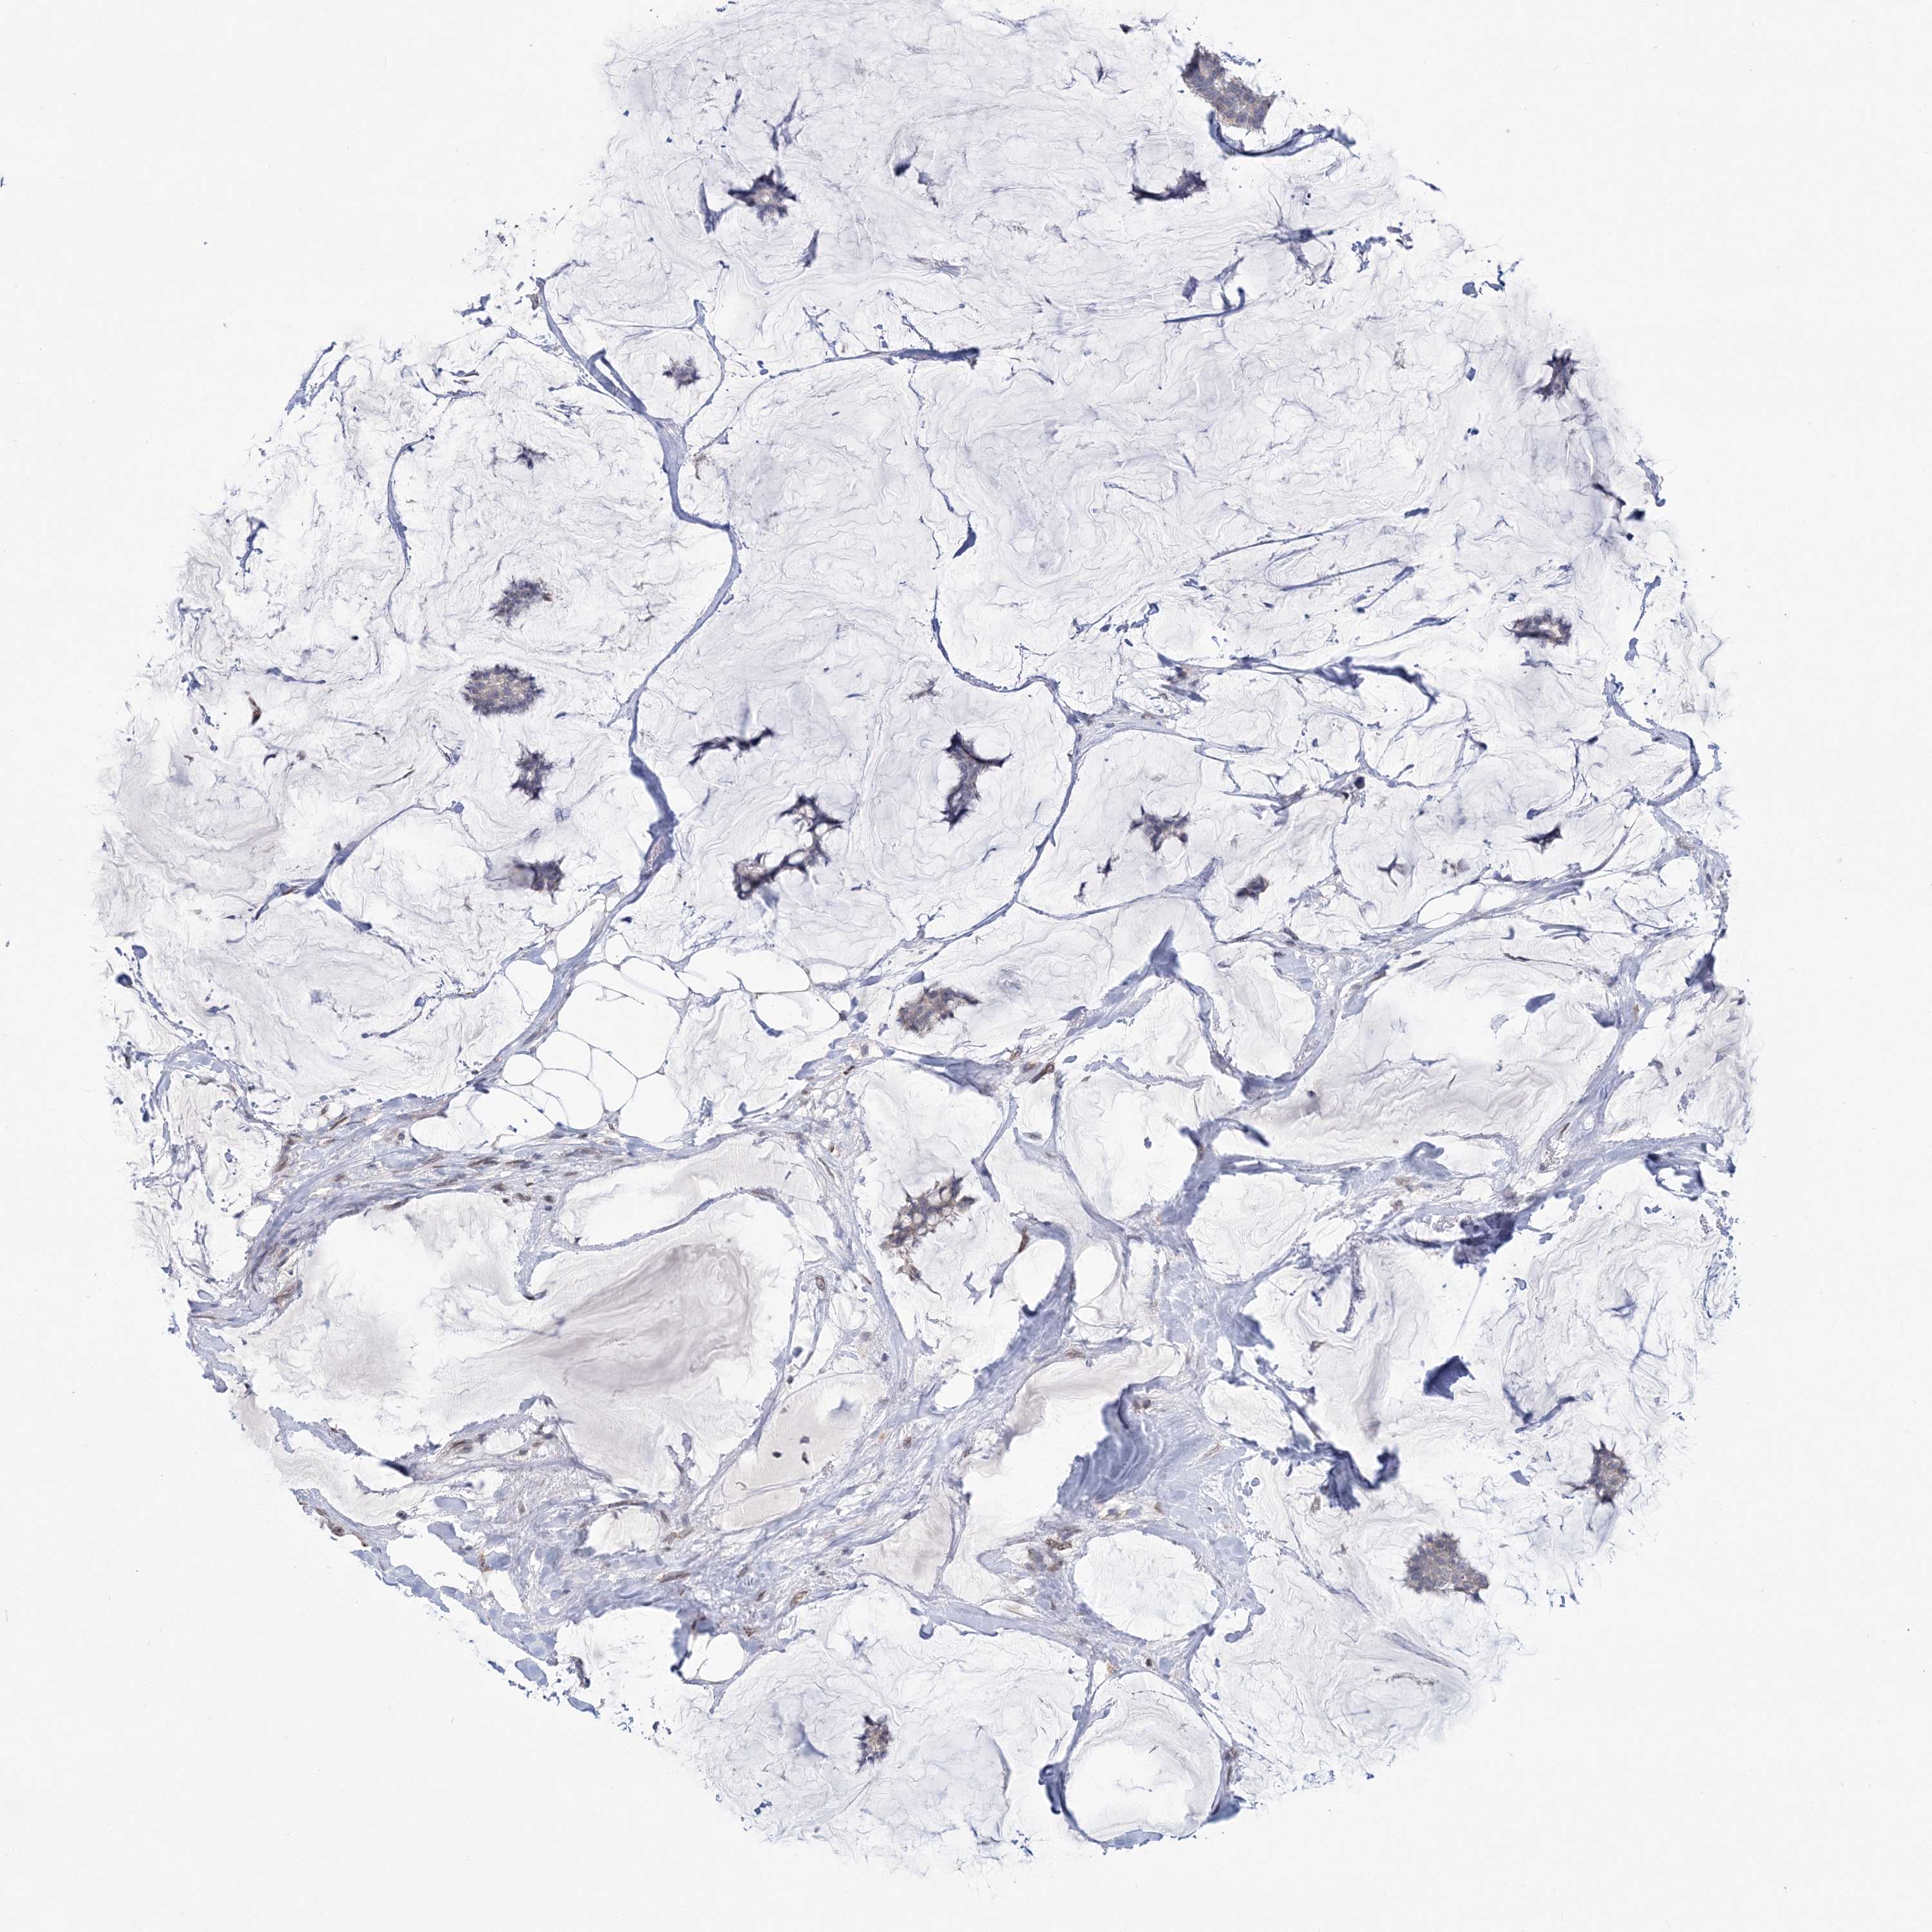

CANCER BREAST CANCER Show tissue menu

BRCA TCGA BRCA VALIDATION PROTEIN EXPRESSION